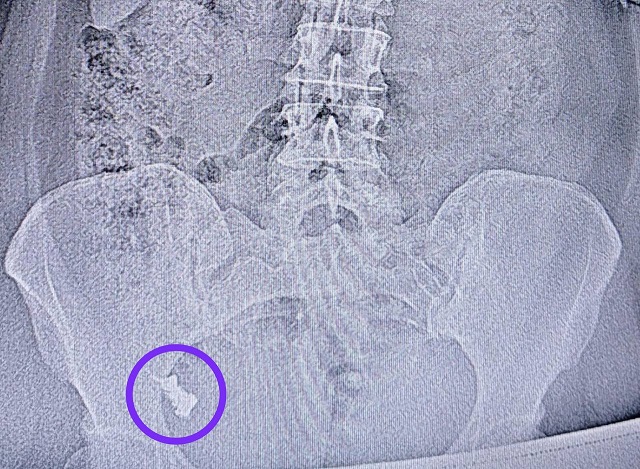

В Казани врачи-эндоскописты Республиканской клинической больницы извлекли из кишечника 50-летней женщины зубной протез, который она случайно проглотила.

Медики пояснили, что от ФГДС женщина неоднократно отказывалась, как и от госпитализации, ссылаясь на то, что протез выйдет сам. Но обойтись без госпитализации не получилось — протез застрял в области перехода тонкой кишки в толстую.

Врач-эндоскопист Наиль Зуфарович Исхаков во время колоноскопии удалил протез. Процедуру делали под контролем анестезиолога-реаниматолога Елены Александровны Чуенковой, ведь протез находился уже в труднодоступном месте.